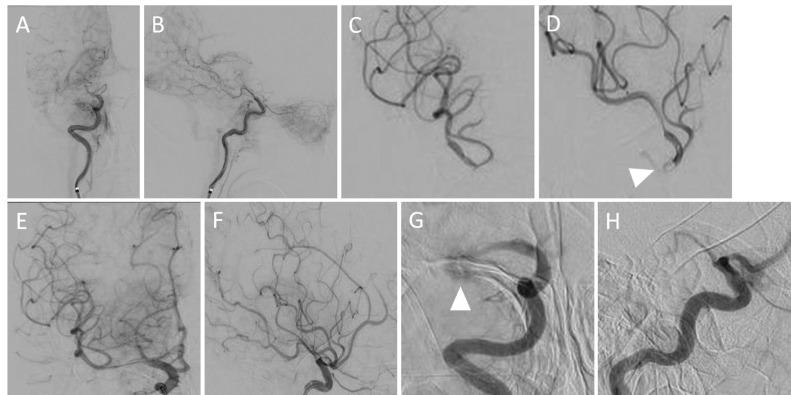

Mechanical thrombectomy (MT) is a highly effective treatment for acute ischemic stroke, and hemorrhagic complications caused by vessel injury are rare. However, there is no evidence regarding the efficacy of MT for multiple large vessel occlusion or its procedural strategy. Herein, we report a case of MT with a stent retriever for multiple large vessel occlusion in the internal carotid artery and middle cerebral artery M1 distal, which resulted in vessel perforation in a single pass. A 79-year-old woman underwent MT for internal carotid artery occlusion, and multiple large vessel occlusion was observed on digital subtraction angiography. A longer and larger stent retriever was selected for thrombus retrieval in a single pass. Immediately after retrieval, digital subtraction angiography revealed internal carotid artery recanalization. Then, extravasation was observed from the M1 distal occlusion. Treatment was interrupted after hemostasis was confirmed. Nevertheless, rebleeding occurred after 4 hours. Emergency trapping was performed, and vessel perforation of >1 mm was observed. When retrieving a thrombus in a single pass with a stent retriever for multiple large vessel occlusion, vessel perforation may occur if the device is selected according to the diameter of the proximal occluded vessel. Based on the type of device, even a single pass may result in vessel perforation. Although aggressive MT intervention should be performed for multiple large vessel occlusion, a device that is appropriate for the pathological condition must be selected.

机械取栓术(MT)是治疗急性缺血性卒中的一种高效方法,由血管损伤引起的出血性并发症较为罕见。然而,目前尚无关于MT治疗多支大血管闭塞的疗效及其操作策略的证据。在此,我们报告一例使用支架取栓器对颈内动脉和大脑中动脉M1段远端多支大血管闭塞进行MT治疗的病例,该操作单次通过导致血管穿孔。一名79岁女性因颈内动脉闭塞接受MT治疗,数字减影血管造影显示多支大血管闭塞。选择了更长、更大的支架取栓器进行单次血栓取出。取出后立即进行数字减影血管造影显示颈内动脉再通。随后,在M1段远端闭塞处观察到造影剂外渗。确认止血后中断治疗。然而,4小时后再次出血。进行了急诊血管封堵,观察到血管穿孔大于1毫米。当使用支架取栓器单次通过取出多支大血管闭塞处的血栓时,如果根据近端闭塞血管的直径选择器械,可能会发生血管穿孔。根据器械类型,即使单次通过也可能导致血管穿孔。尽管对于多支大血管闭塞应积极进行MT干预,但必须选择适合病情的器械。